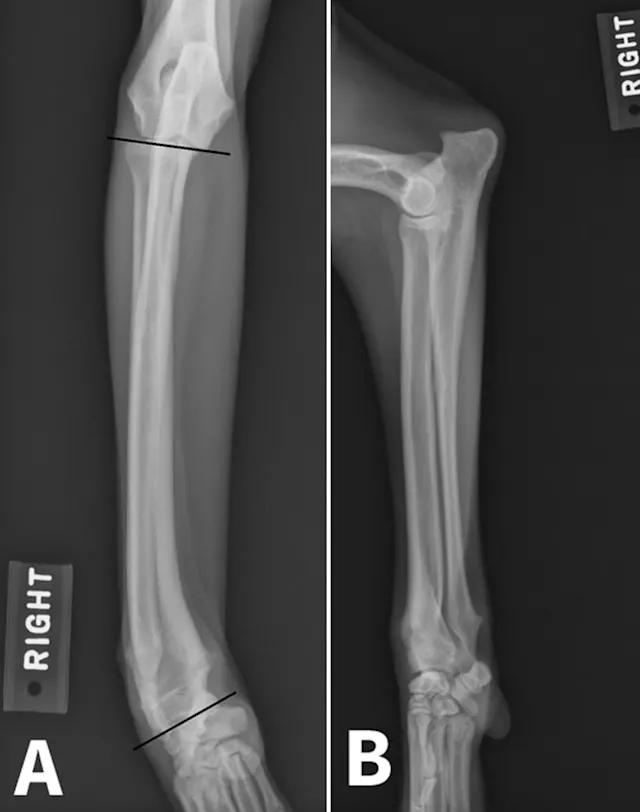

Angular limb deformities (ALD) can occur in both small and large companion animals and can result in significant functional impairment. Although any long bone in dogs can be affected, ALD are most commonly seen in the antebrachium, as well as in the femur and tibia secondary to patellar luxation.1 Deformities may develop secondary to abnormalities in bone growth (eg, premature closure of physis following trauma), bone formation (eg, disease process disrupting normal endochondral ossification; hypertrophic osteodystrophy, retained cartilaginous core, nutritional disorders), or bone healing (eg, fracture malunion).

Figure 1. Radial valgus and external torsion.

Physeal trauma is a common cause of ALD, particularly when paired bones are involved. Distal forelimb trauma in immature patients can cause a compression injury (Salter V fracture)2 to the conical-shaped distal ulnar physis, leading to premature closure of the distal ulnar physis. This results in cessation of ulnar growth. Although the radius will continue to grow in affected patients, valgus deviation, cranial bowing of the radius, and torsional deformity can typically develop as a result of the constraining effect of the ulna.3